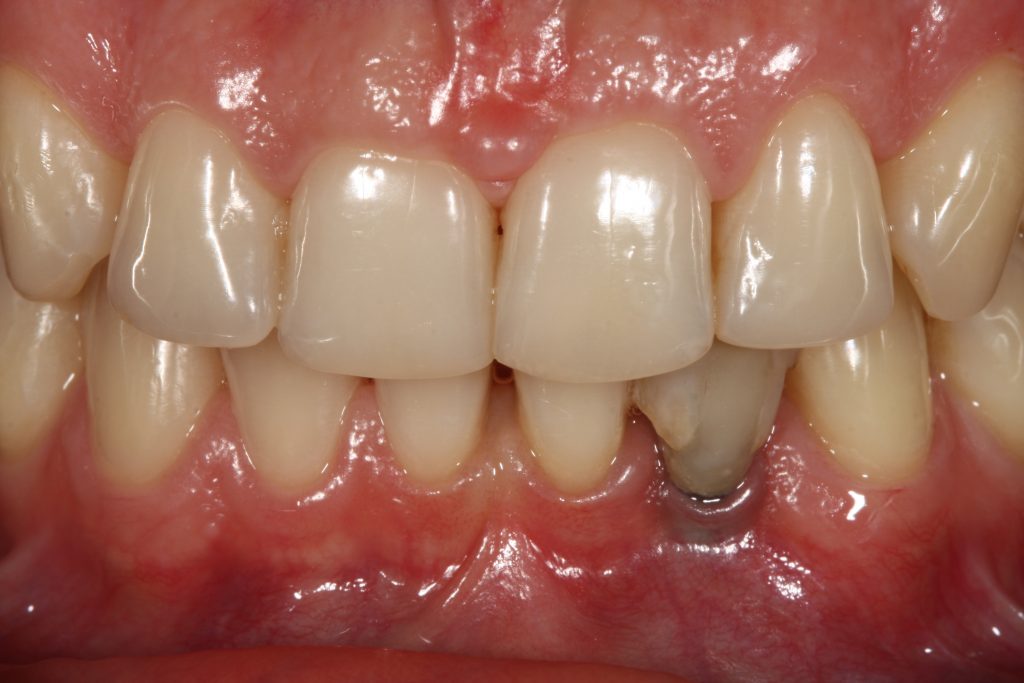

The consequence of marginal peri-implant mucosa migration, as a result of early marginal bone loss, has a major implication in the aesthetics of the restoration, particularly in the anterior area.